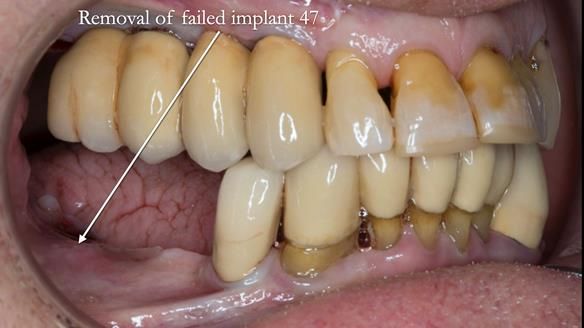

We began with the lower jaw.

A posterior implant 47 had lost integration and was infected. This was removed.

Ken did not want further implant surgery.

Instead, we made a Scandinavian-style, metal-based lower RPD.